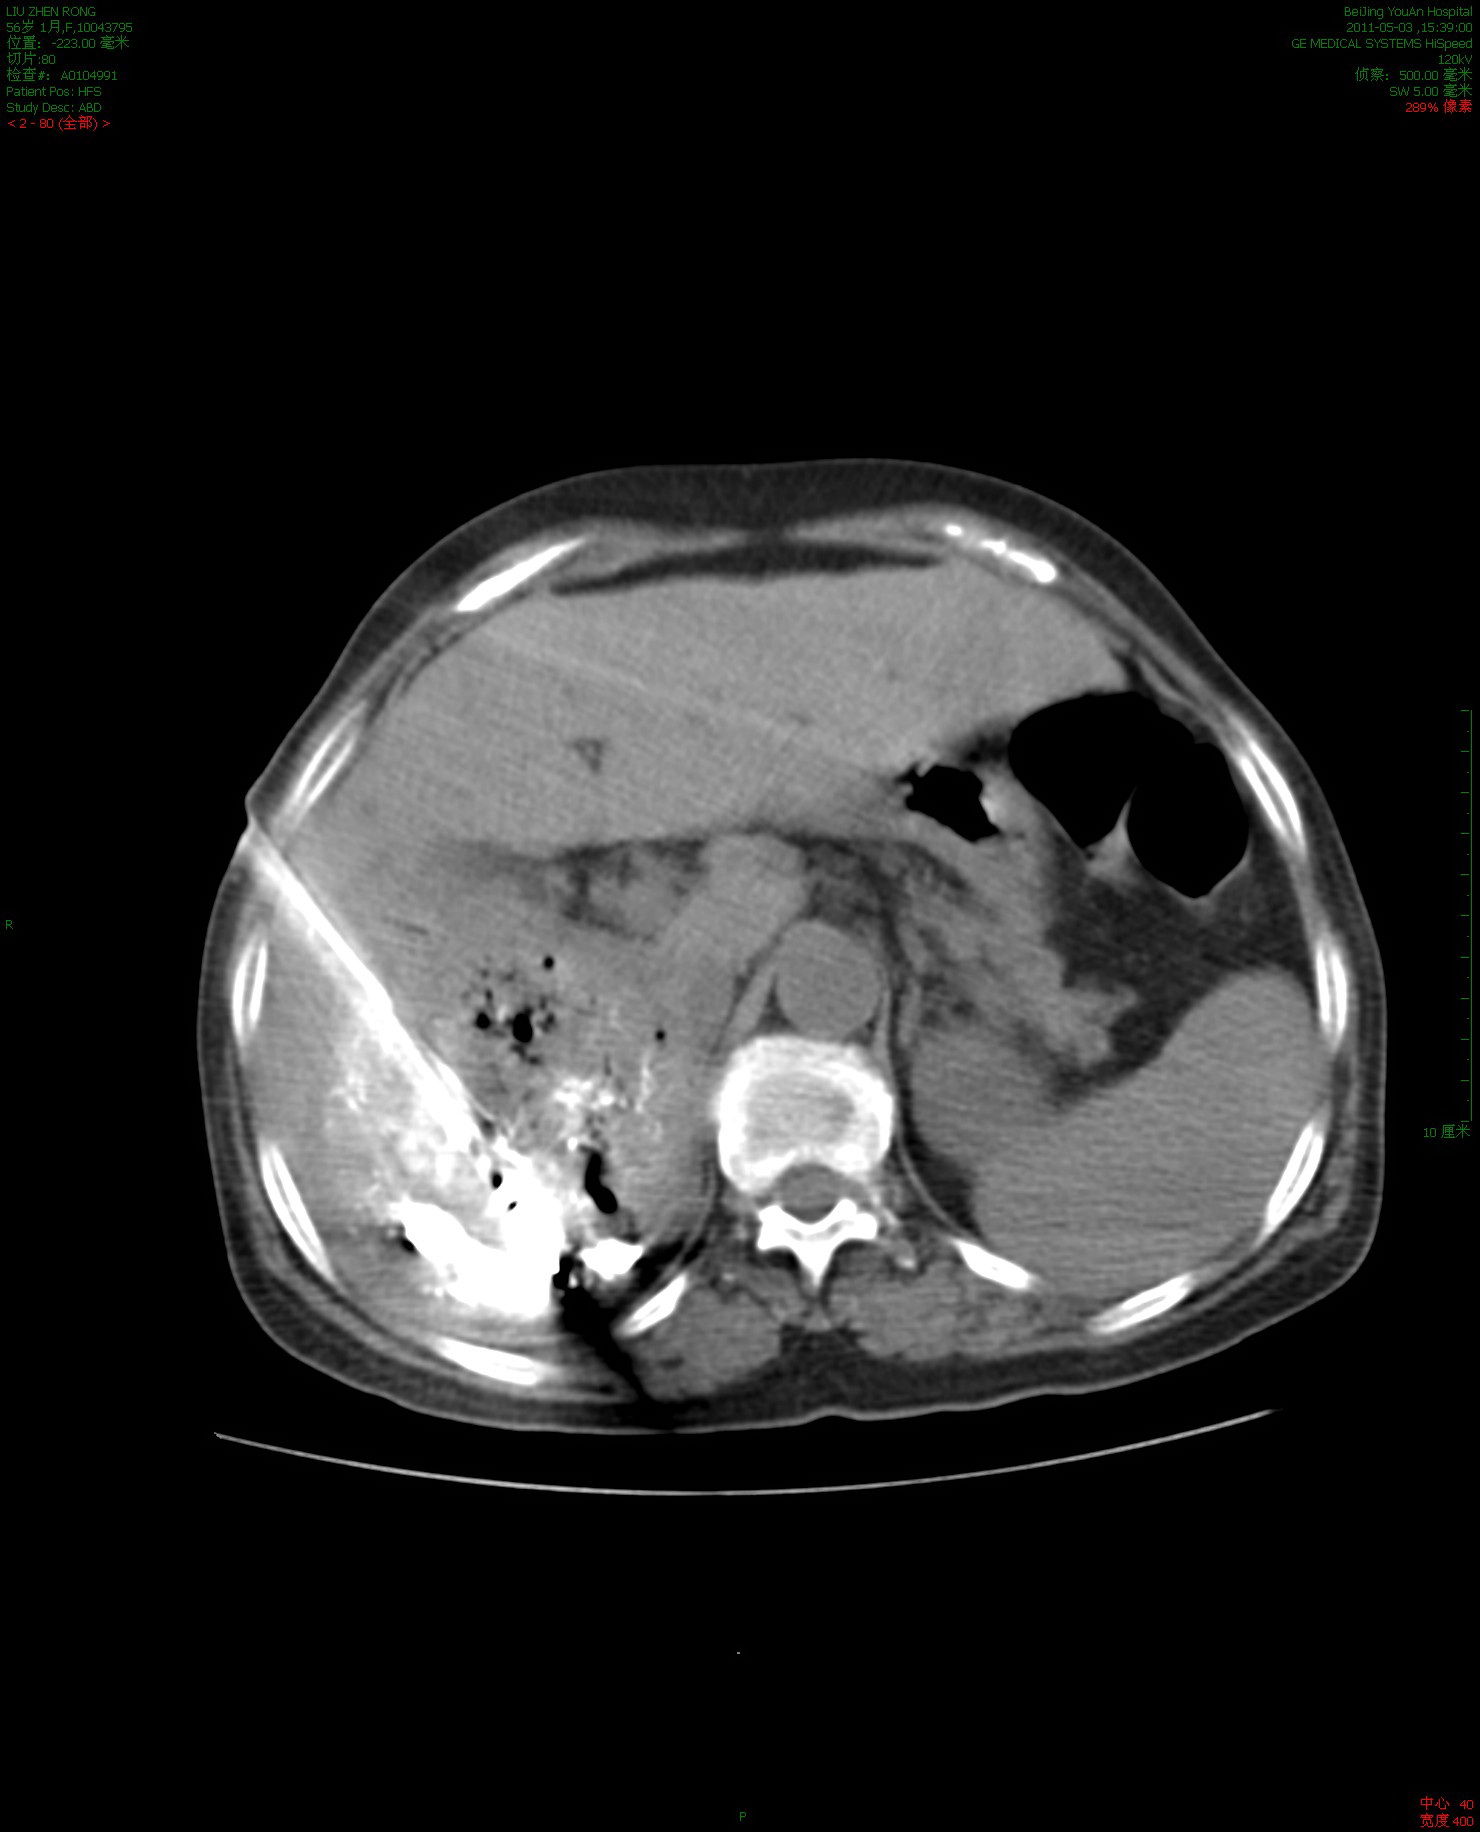

2、隨著經皮消融術在肝腎前列腺等臟器的運用,其在肺部腫瘤上的應用也日益增多目前國內外常用消融技術包括的熱消融,如射頻微波激光高強度聚焦超聲等以及冷消融技術如氬氦刀等,在肺部以射頻治療的經驗最為豐富經皮消融治療的優勢在于定位準確療效高創傷小并發癥低幾乎無副作用;在過去的三十年中,肝癌的診斷和治療方法穩步增加各種影像學的發展為肝癌的早期診斷提供了極大的幫助,像腹部B超CTMRIPETCT造影技術等目前的治療方法也有極大的發展,包括手術切除腫瘤,肝移植,TACE射頻微波治療無水酒精分子靶向藥物治療等治療 雖然診斷和治療方法較以前有了很大的提高,但是,每年;直徑5cm至7cm以上的腫瘤應選擇最新第三代超級針經美國RITA公司最新研發第三代超級多極針,一次消融直徑達7cm以上,并使用了特殊注射泵,使熱傳導更快更均勻,治療時間大幅縮短,治療大腫瘤效果更確切,病人更輕松 一般采用局麻,CT掃描定位,按測定的距離和角度對腫瘤進行經皮穿刺,將電極針刺入。